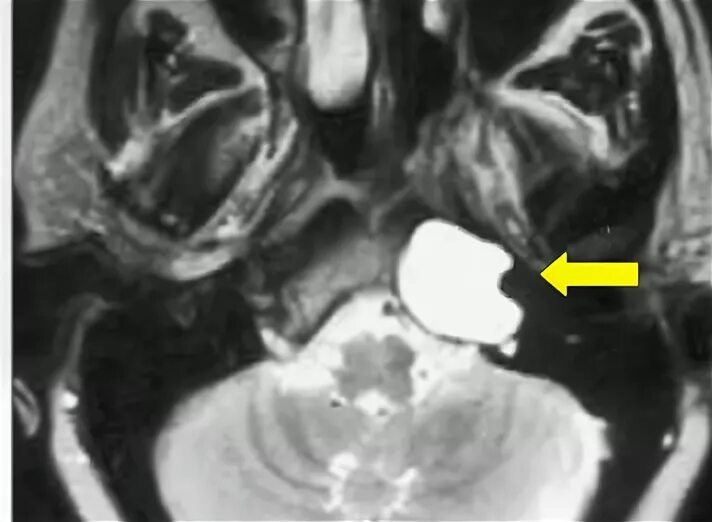

Мрт головного мозга мосто мозжечкового угла